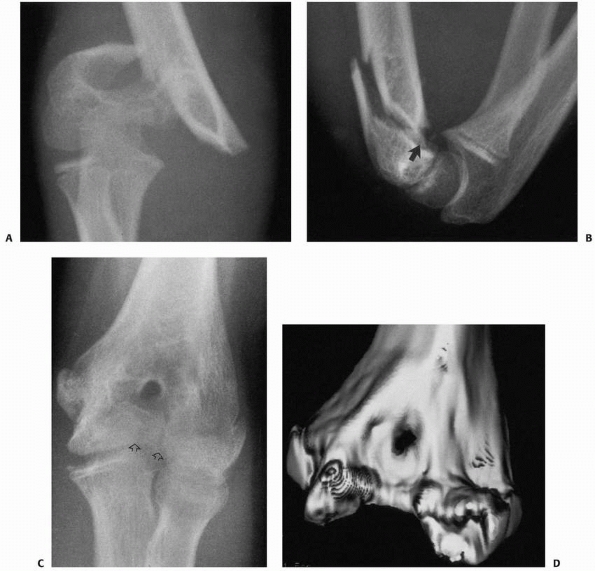

III supracondylar fracture but do not show full detail of the distal

epiphyseal fragment. T-condylar fractures (Fig. 14-16)

![]() |

FIGURE 14-16 Occult T-condylar fracture. A. Original radiographs appear to show a type III posteromedial supracondylar fracture. B. After manipulation, the vertical intercondylar fracture line (arrows) was visualized.

FIGURE 14-17 This 1.2-year-old girl sustained a fracture that on the anteroposterior view (A) appears like an elbow dislocation and on the lateral view (B) has the appearance of a lateral condyle fracture. C.

Arthrography showed the outline of the entire cartilaginous epiphysis. This is an epiphyseal separation with a metaphyseal fragment (Salter-Harris type II). |